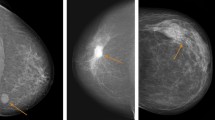

Mammographic tumour appearance is related to clinicopathological factors and surrogate molecular breast cancer subtype